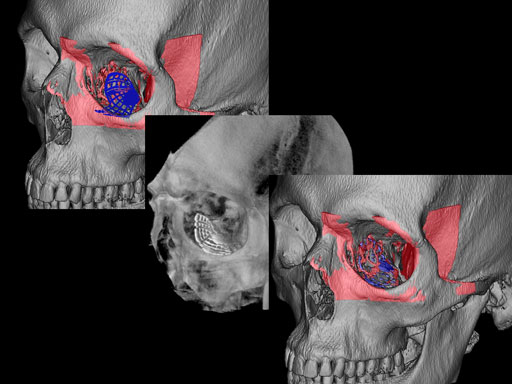

Fig 3 Implant placement according to the orbital landmarks: 1 Orbital rim, 2 Inferior orbital fissure, 3 Posterior orbital ledge, 4 Transition between the medial wall and orbital floor, 5 Optic canal, 6 Lacrimal fossa.

30-year-old male with fracture of left orbital floor and involvement of medial wall.

Case provided by Marc C Metzger, Freiburg, Germany

Fig 1 CT scan with fused image of virtual prebent orbital plate.